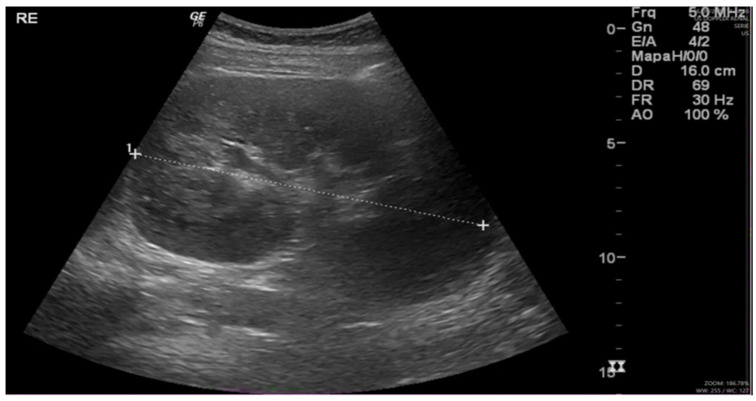

摘要:肾斑疹是一种罕见的慢性肉芽肿性疾病,常伴有免疫抑制和持续的革兰氏阴性感染,尤其是大肠杆菌。病例介绍:我们报告一例31岁女性高血压,妊娠期糖尿病,引产后子宫刮除为先兆子痫在23周。术后出现尿脓毒症。影像学显示双侧肾肥大,实验室检查显示急性肾损伤(KDIGO III期)、贫血和血小板减少症。血液和尿液培养培养出大肠杆菌。肾活检证实斑疹,显示pas阳性Michaelis-Gutmann小体和Von Hansemann细胞。患者对长期抗生素治疗和支持性护理有反应。讨论与结论:本病例强调了在非典型尿路感染和肾脏病患者中考虑肾脏畸形的重要性,特别是在产科环境中。组织病理学确认是必要的,及时使用细胞内活性抗生素治疗可导致良好的结果。早期诊断对预防不可逆肾损害至关重要。

Introduction: Renal malacoplakia is a rare chronic granulomatous disease, often associated with immunosuppression and persistent Gram-negative infections, particularly Escherichia coli. Case Presentation: We present a case involving a 31-year-old woman with hypertension, gestational diabetes, and prior uterine curettage after labor induction for preeclampsia at 23 weeks. She developed urinary sepsis post-procedure. Imaging revealed bilateral nephromegaly, while laboratory tests showed acute kidney injury (KDIGO stage III), anemia, and thrombocytopenia. Blood and urine cultures grew Escherichia coli. Renal biopsy confirmed malacoplakia, demonstrating PAS-positive Michaelis-Gutmann bodies and Von Hansemann cells. The patient responded to prolonged antibiotic therapy and supportive care. Discussion and Conclusion: This case highlights the importance of considering renal malacoplakia in patients with atypical urinary tract infections and nephromegaly, particularly in obstetric settings. Histopathological confirmation is essential, and timely treatment with intracellularly active antibiotics can lead to favorable outcomes. Early diagnosis is critical to prevent irreversible renal damage.